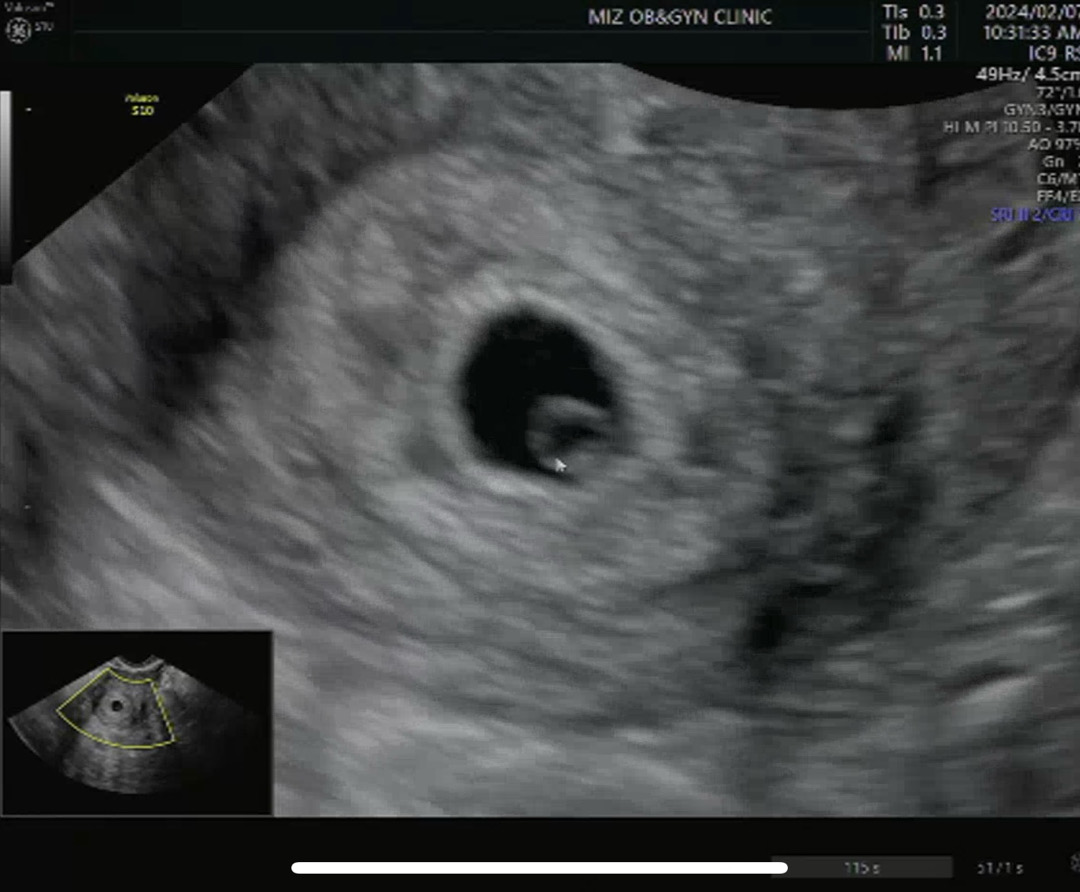

아기집&난황 보고왔어요! 히히

저번주 토욜 메인 병원에서 볼때는 난황도 작았는데 오늘 서브 병원가서보니 아기집도, 난황도 좀 커져있네요!! 생리주기가 한 30일 정도라 좀 늦게 본 편인데 위치랑 모양도 좋다고하셔서 걱정했던 마음이 한결 편안해졌네용ㅎㅎ 담주 수욜에 메인 병원 다시 가는데 이 때는 심장 소리 들을 수 있기를...😖